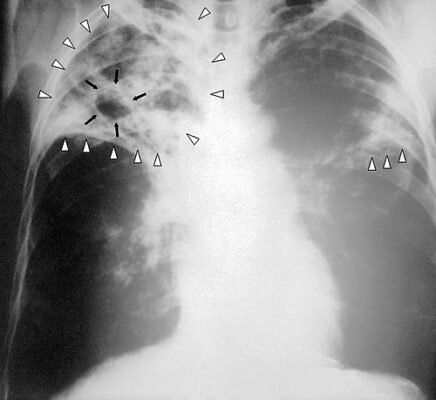

Діагностика: полювання на невидиме

Важливо звернути увагу, якого мастера потребує діагноз. Старанний лікар витончено вивчає таємні знаки, які проявляються у загадкових плямах на рентгенівському знімку.

- Рентгенографія — знайомимося з кольорами.